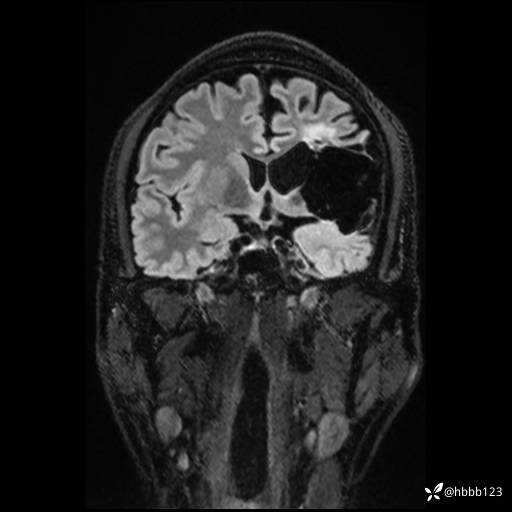

CUBE FLAIR冠状位: